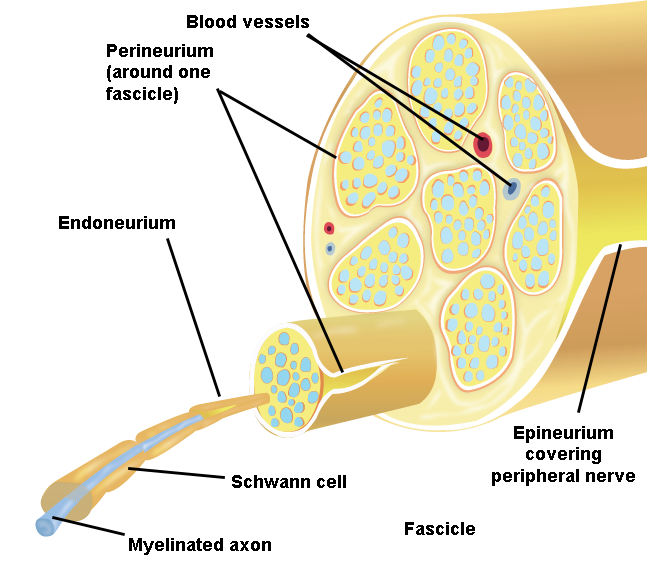

Illustration 1. Anatomy of Peripheral Nerves

II. Anatomy of Peripheral Nerves

Peripheral nerves are composed of bundles of neurons, or nerve fascicles, which are enclosed by a connective tissue called the perineurium.

- Fascicles are further bundled and held together by the loose connective tissue of the endoneurium.

- This nerve complex is enclosed within epineurium, the outermost layer of a peripheral nerve.